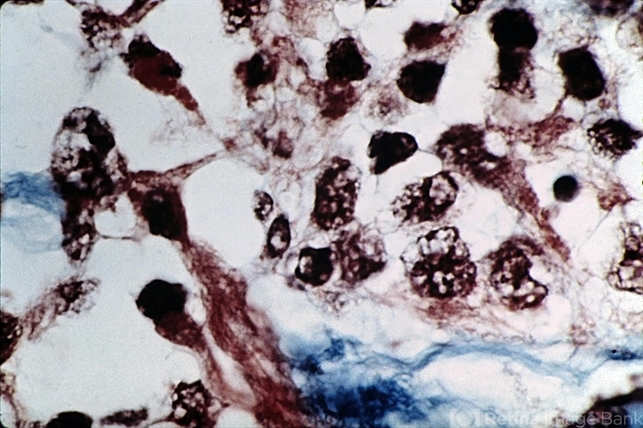

- Differentiated rhabdomyosarcoma. Cross-striations are relatively easy to find (trichrome stain x630).